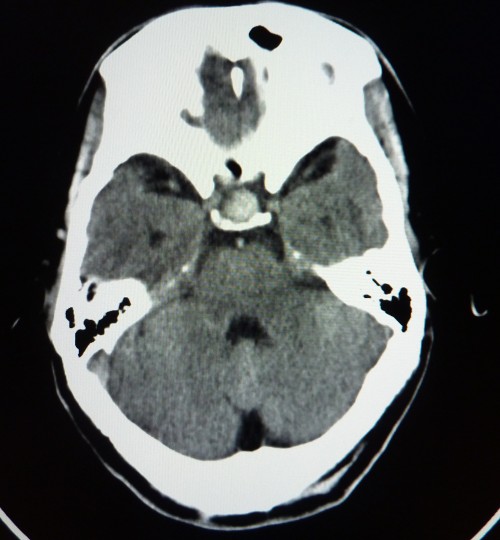

标题: CT26504:男,45岁,头痛伴呕吐两星期。 [打印本页]

标题: CT26504:男,45岁,头痛伴呕吐两星期。

鞍内可见高密度类圆形影,鞍背骨质吸收,支持垂体瘤伴出血,建议mri检查。

垂体增大,密度明显增高,考虑垂体瘤卒中,建议mr

考虑垂体瘤、a瘤、鞍区脑膜瘤,建议mri